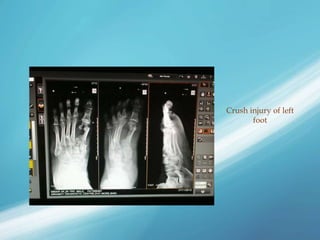

Crush injury of left

foot

Crush injury ofleft foot